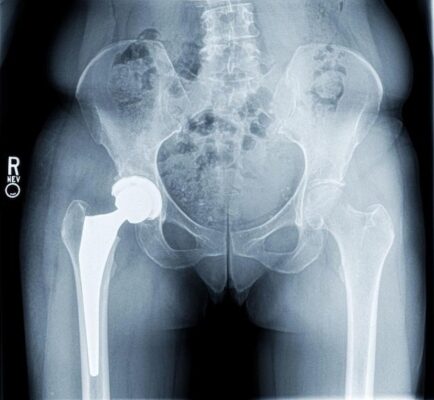

Bệnh nhân nam, 67 tuổi yêu cầu được khám vật lý trị liệu 6 tháng sau phẫu thuật thay khớp háng toàn phần bên phải. Ông cho biết rằng ông tiếp tục bị đau chân, chủ yếu ở vùng trước giữa đùi. Theo lời bệnh nhân, ông đã được tập vật lý trị liệu tích cực sau phẫu thuật tại một trung tâm phục hồi chức năng trong 1 tháng. Trung tâm đó đã cung cấp ông một chương trình tại nhà rất tốt, và ông tiếp tục thực hiện mà không gặp khó khăn gì. Với sự chấp thuận của bác sĩ, bệnh nhân tăng tiến sang tập thể dục ba lần một tuần tại một trung tâm thể hình ở địa phương.

Xét nghiệm máu sau phẫu thuật được thực hiện gần đây do bác sĩ chỉ định cho thấy tất cả các giá trị đều trong giới hạn bình thường. Phiếu đọc chụp X quang sau phẫu thuật cho thấy khớp giả ở vị trí tốt. Bệnh nhân không có bệnh sử bị trật khớp háng.

Đau vẫn tiếp tục ở chân bệnh và không có khả năng là do gãy xương; do đó kỹ thuật viên đã khám bệnh nhân để xem có thể có sự chênh lệch về chiều dài chân hay không. Trong trường hợp này, bệnh nhân có sự chênh lệch khoảng 1⁄2 inch (12,7 mm), với chân bên phải ngắn hơn chân bên trái. Khi được hỏi, bệnh nhân trả lời rằng ông không biết rằng có sự khác biệt về chiều dài như vậy. Người kỹ thuật viên đã thực hiện can thiệp trước đây dường như đã không thông báo cho bệnh nhân về sự khác biệt chiều dài chân này.

Trong trường hợp này, kỹ thuật viên đã gửi một ghi chú đến bác sĩ yêu cầu xem xét cung cấp một miếng đệm lót giày để xem triệu chứng đau khi đi có giảm/mất hay không. Bác sĩ phẫu thuật đồng ý với đề nghị này và bệnh nhân được cung cấp một miếng đệm lót. Trong vòng 2 tuần, bệnh nhân đã hết đau khi đi. Sau đó, bệnh nhân đã chỉnh lại tất cả các đôi giày của mình bằng các miếng đế nâng 1⁄2 inch vĩnh viễn, và không còn gặp khó khăn gì nữa.